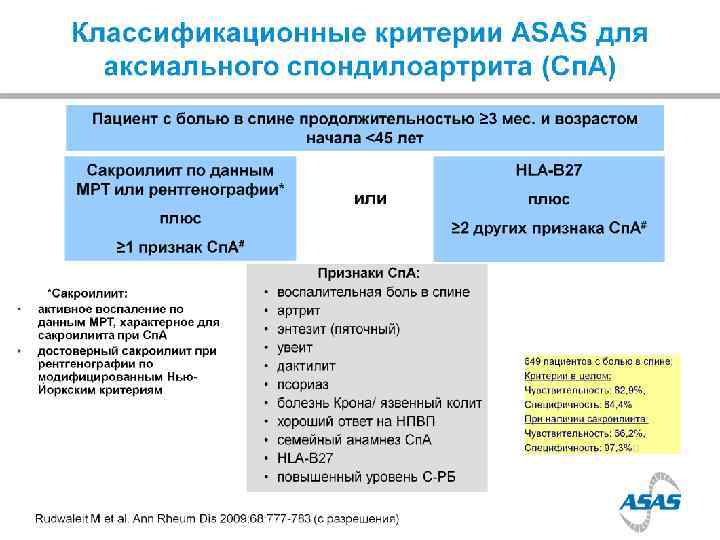

Prevalence of Axial Sp. A in US (NHANES study) chronic back pain in 20% of population IBP in 7% of population; > in younger adults Ax. Sp. A (including AS) in 1. 4% AS in 0. 5% AS nr. Ax. Sp. A MALES=FEMALES (Ax. Sp. A); M: F=2: 1 (AS) 12% in 2 years